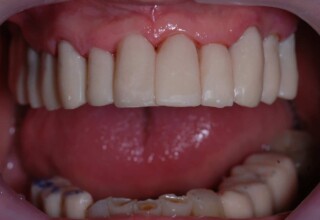

Ολική Στοματική Αποκατάσταση σε Εμφυτεύματα με διαφορετική προσέγγιση στην Άνω και Κάτω Γνάθο

Κάτω γνάθος: εξαγωγές, άμεση τοποθέτηση εμφυτευμάτων και άμεση φόρτιση(την ίδια ημέρα) με προσωρινή γέφυρα

Άνω γνάθος: σταδιακές εξαγωγές, σταδιακή τοποθέτηση εμφυτευμάτων και σταδιακή ενσωμάτωση τους στην προσωρινή γέφυρα ώστε η ασθενής να μην μείνει ούτε μια ημέρα χωρίς αποκατάσταση. Στόχος η συνεχής λειτουργική και αισθητική αποκατάσταση της ασθενούς χωρίς άμεση φόρτιση των εμφυτευμάτων λόγω ανατομικών ιδιαιτεροτήτων.

Χρησιμοποιήθηκαν παλαιές χαμογελαστές φωτογραφίες της ασθενούς γιατί είχε χαθεί τελείως το φυσικό σχήμα των δοντιών εξαιτίας των πολλαπλών προσθετικών προσπαθειών που είχαν γίνει στο παρελθόν. Μεταφέρθηκε στην προσωρινή γέφυρα η σχέση των φυσικών δοντιών μεταξύ τους άλλα και με τα χείλη. Δοκιμάστηκε η φώνηση και η μάσηση με δυο διαφορετικές προσωρινές άνω γέφυρες και εκτιμήθηκε η αισθητική απόδοση τους. Αφού επιτεύχθηκαν σε βαθμό ικανοποιητικό η φώνηση και η αισθητική εμφάνιση της οδοντοφυΐας, η προσωρινή αποκατάσταση χρησιμοποιήθηκε ως οδηγός για την τελική.

Ενδιάμεσο

Τελικό